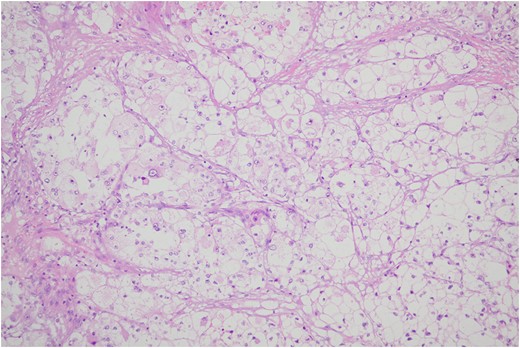

Histologic sections of the mass show distinct variably sized and shaped collections of uniform polygonal tumor cells, separated by fibrovascular septa and delicate capillary-sized vascular channels lined by flattened endothelium at low magnification (Fig. 5). Within the tumor nests, there is loss of cellular cohesion and necrosis of the centrally located cells in the nests results in the pseudo-alveolar pattern (Fig. 6). Vascular invasion is also present (Fig. 7). The individual tumor cells have distinct cell borders and abundant eosinophilic to clear, somewhat granular cytoplasm surrounding a central nucleus with variably sized nucleolus. Nuclear atypia is rarely seen. Mitotic figures are uncommon. The cells contain rhomboid or rod-shaped crystalline inclusions that are faintly apparent on routine histology and are better demonstrated with periodic acid-Schiff stain after diastase digestion (Fig. 8).

Tumor cells are arranged in organoid or nesting pattern. The nests are vary in size and shape and are separated by delicate thin fibrous septa containing vascular channels.